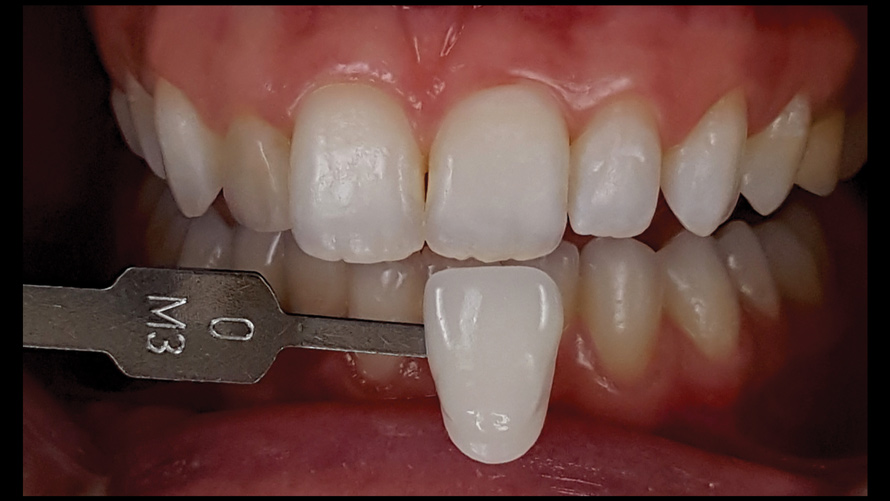

(18.) Tooth shade analysis of value, chroma, and hue taken with a smartphone and an EALS device.

Figure 18

(19.) Tooth shade analysis of value, chroma, and hue taken with a smartphone and an EALS device.

Figure 19

Shade Selection and Laboratory Communication

The most utilized intraoral photographs in the field of dentistry are perhaps those that capture shade information (Figure 18 and Figure 19). The analysis of color (ie, value, chroma, hue) in dentistry is a critical step in the fabrication of esthetic indirect restorations, such as all-ceramic crowns and porcelain laminate veneers. The ability to properly communicate this information with the dental laboratory is essential to ensure an appropriate shade match, a reduction in chairtime and overhead, and most importantly, a satisfactory patient experience and treatment outcome. In recent years, the use of polarized light photography as an aid in the shade selection process has become extremely popular. For some EALS devices, special polarizing filters have been specifically designed to fit over the light-emitting portion of the device (Figure 20 and Figure 21). The images produced using polarized light photography demonstrate an elimination or reduction in the specular reflection of hard and soft tissue, resulting in a matte-finish appearance of the dentition and gingiva. These types of photographs aid the ceramist in identifying areas of opacity and translucency, crack lines, hypo- or hypercalcification, and other internal features of the dentition that may not be readily visible without such a filter (Figure 22).